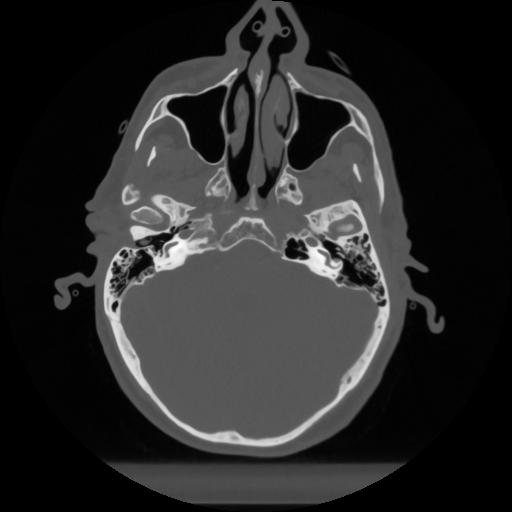

12 P.BLANDAS,,Vol,0.5,P.BLANDAS,,